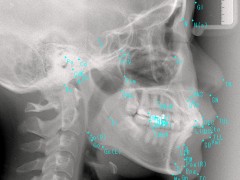

X線写真、口腔内写真、歯型の採取、唾液検査(むし歯のリスクを調べます)、必要に応じて、低被ばく線量の最新CT撮影、コンピュータによる顎運動検査・筋電図検査(K7)などを行う場合もあります。